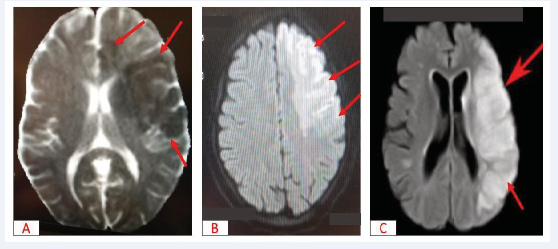

The initial diagnosis of non- compaction of the left ventricle complicated by intra- VG thrombi was accepted. The patient was treated with furosemide 80 mg daily, enalapril, spironolactone and enoxaparin in curative doses. The immediate course was marked at 48 hours by the sudden onset of massive left hemiplegia associated with Broca’s aphasia and respiratory distress. Magnetic resonance imaging of the brain revealed diffuse cortico-subcortical hypersignal areas in the left frontal, left parieto-temporo-occipital and left caudo-capsulo-lenticular regions, suggesting a recent left hemispheric ischaemic stroke (Figure 2).

Figure 2: Brain MRI showing

A: Left fronto-temporal-parietal hyposignal suggestive of recent constituted ischaemia, T1 sequence (red arrow)

B: Left fronto-temporal-parietal hypersignal suggestive of recent constituted ischaemia, diffusion sequence (red arrow)

C: Left fronto-temporal-parietal hypersignal suggestive of recent constituted ischaemia, sequence, 3DTOF, transventricular slice (red arrow)